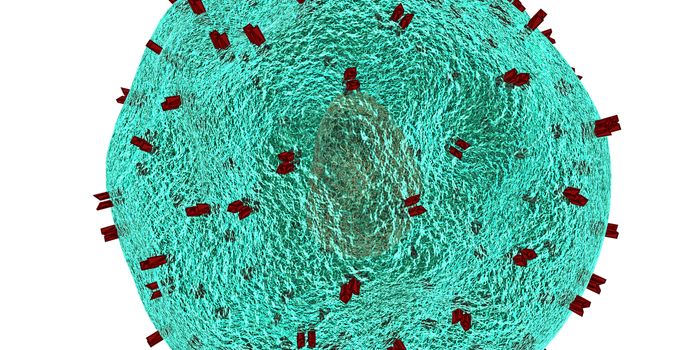

DEC 15, 2018Cell & Molecular BiologyResearchers have been trying to create a vaccine for HIV, the virus that causes AIDS, for decades.